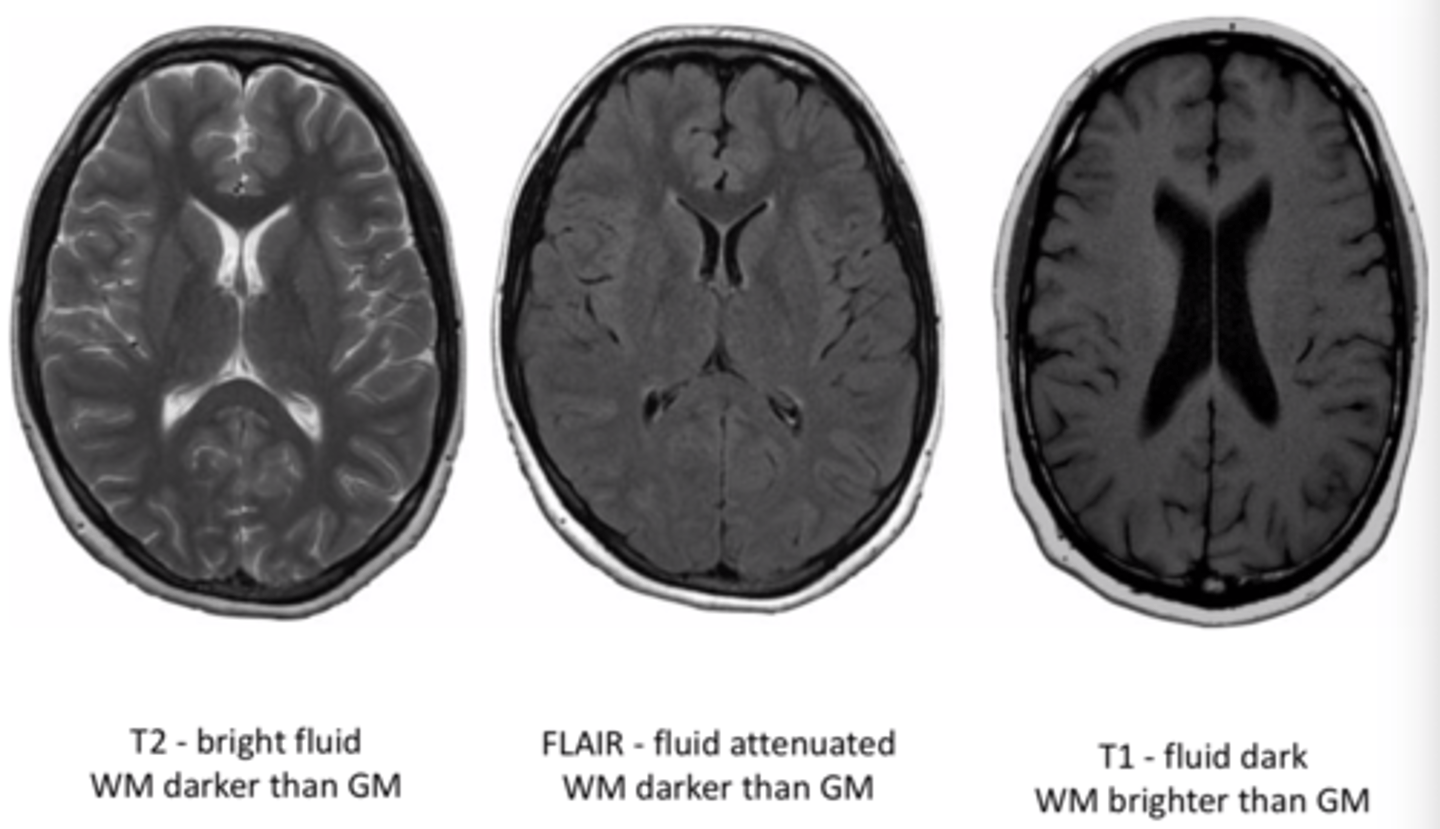

MRI T1 images

Fat is white

Water is dark

<p>Fat is white </p><p>Water is dark</p>

MRI T2 images

Fat is dark

Water is white

<p>Fat is dark</p><p>Water is white</p>

MRI flair images

Similar to T2, but CSF is dark

<p>Similar to T2, but CSF is dark</p>